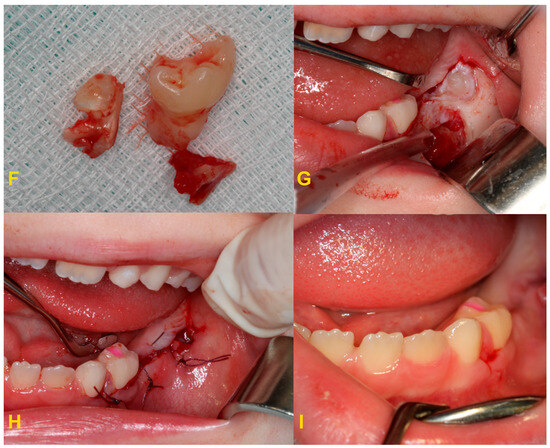

Figure 8.

Severe reinclusion of tooth no. 75 causing infraposition of the tooth no. 36: (A) panoramic X-ray, (B) preoperative intraoral photography—teeth nos. 75 and 36 are missing in the oral cavity, (C) intraoral photography—after elevation of the mucoperiosteal flap, (D) intraoral photography—osteotomy, (E) intraoral photography—crown–root separation, (F) fragments of extracted tooth no. 75, (G) intraoral photography—osteotomy and exposure of tooth no. 36, (H) intraoral photography—stitching the wound, and (I) intraoral photography—healing on the 7th day after the procedure.

In the case of severe infraocclusion, the treatment of choice is tooth extraction. The procedure can be very complicated due to the tilt of the teeth relative to the gap and the difficult access, as well as root dilaceration. The adjacent teeth could be uprighted with an orthodontic appliance to make the surgical procedure easier. Often, the procedure requires coronal–root separation of the tooth, mucoperiosteal flap elevation, and osteotomy [37,38,39,40]. In the case of reincluded teeth into the maxillary sinus, it may open, and cause complications related to the maxillary sinus, such as the oro–sinus communication, oro–sinus fistula, or maxillary sinusitis. The roots of submerged teeth in the mandible may be located deep in the body of the mandible and surrounding or entwining the inferior alveolar nerve canal or the lower border of the mandible. If it is necessary to remove a tooth, it may result in disruption of the neurovascular bundle, bleeding, damage to the inferior alveolar nerve, or sensory disturbances. If there is significant bone loss during the extraction of such a tooth, the area may require miniplate osteosynthesis. This is a place of reduced resistance and may result in a fracture of the mandible [37,38,39,40,41,42,43].